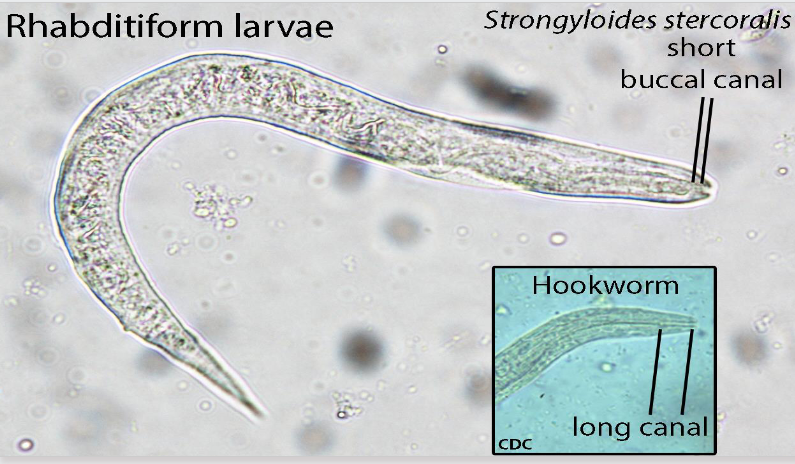

rhabditiform vs filariform

diagnosis of strongyloides stercoralis

Look for rhabditiform larvae in concentrated fecal specimens

Must differentiate from hookworm larvae

strongyloides stercoralis rhabditiform larvae

Short and sexy

first-stage larva as passed in the feces

esophagus is short (much less than 40% of the body) and distinctly bulbed, the short mouth capsule, and the large genital rudiment (GR)

the latter 2 characteristics distinguish these larvae from those of the hookworms

simple pointed tail

hookworm rhabditiform larvae

Long buccal cavity

More than the width of the body

Genital primordium NOT visible

Esophagus is bulbed

strongyloides rhab vs filariform

rhabditiform: short buccal cavity; esophageal bulb; pointed tail; large genital primoridum

hookworm rhab vs filariform

rhabditiform: long buccal cavity; esophageal bulb; straight tail; small genital primordium

strongyloides rhab vs hookworm rhab

strongyloides: short buccal cavity; esophageal bulb; pointed tail

hookworm: long buccal cavity; esophageal bulb; straight tail